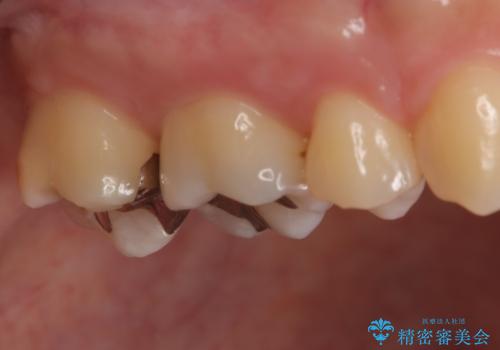

- 金属を外してセラミックを入れたいことを主訴に来院された患者さんです。

セラミックインレーにて修復を行いました。